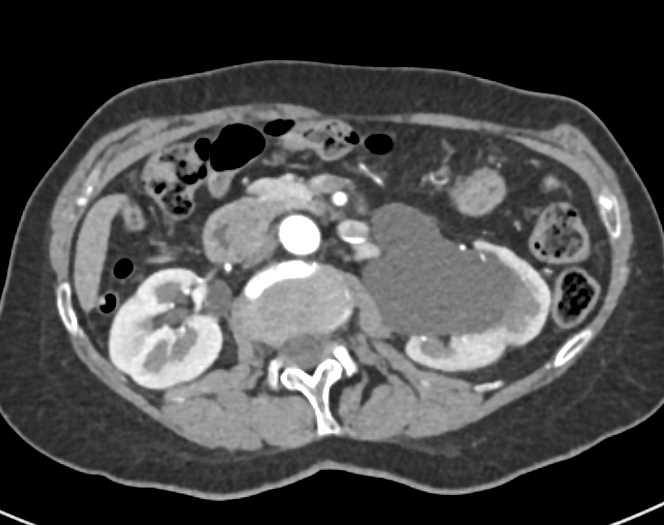

Transitional Cell Carcinoma Left Kidney